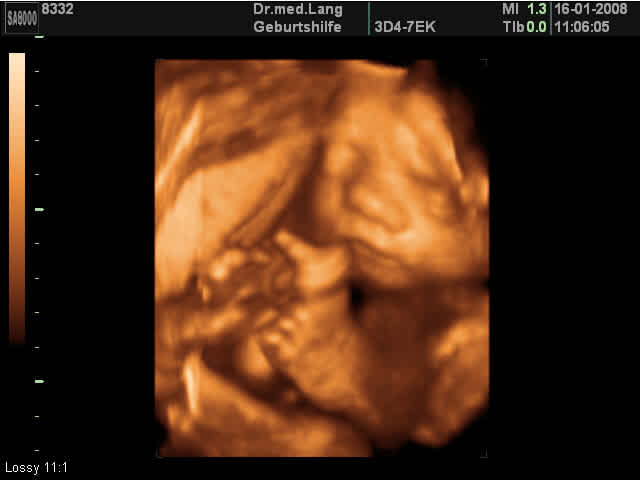

Organscreening Ein Organscreening ist eine Ergänzung Ihrer MutterKindPass Untersuchungen Im Rahmen dieser zusätzlichen Ultraschalluntersuchung werden viele Details beim Kind dargestellt Besonders werden das Gesicht, das Herz und das Gehirn und die gesamte Anatomie des Kindes begutachtet Die Untersuchung erfolgt nach internationalen Standards und Richtlinien und erfordert eine fundierte. Kann man 3D Ultraschall in der 26 ssw machen?. Hier wird in der Regel ein 3DUltraschall eingesetzt SSW 26 SSW 27 SSW 28 SSW 29 SSW 30 SSW 31 SSW 32 SSW 33 SSW 34 SSW 35 SSW 36 SSW 37 SSW 38 SSW 39 SSW 40 SSW Vornamen für euer Baby Liste Die 0 beliebtesten Vornamen 21 in Deutschland für Mädchen und Jungen.

In der 26 Schwangerschaftswoche passiert Aufregendes im Leben des Fötus Seine Augen öffnen sich Die 26 SSW ist ein guter Zeitpunkt für einen 3DUltraschall, auch BabyTV genannt Bei. SSW das Gestationsalter um 4 e unterschätzt (3,7 mm Differenz im CRL), dafür in der 11–14 SSW um einen (0,8–1 mm) überschätzt Die aus dem Jahr 19 stammenden HadlockKurven unterschätzen das Gestationsalter in der 6 SSW um 3 e (2,7 mm) und überschätzen es in der 14 SSW um 2 e (4,8 mm). Antwort auf Gewicht Baby in der 26 ssw (253) Hallo, 1 in der 26SSW sollte das Gewicht zwischen Gramm liegen und der Mittelwert liegt hier bei 913 Gramm 2 mit 600 Gramm wäre das Gewicht also deutlich zu niedrig Jedoch ist es wichtig, zu wissen, dass es zu diesem frühen Schwangerschaftszeitpunkt bei der Berechnung über die Ultraschallsoftware noch größerer Fehler geben kann.

Oder ist das noch zu früh?. Das Baby in der 26 SSW In der 26 Schwangerschaftswoche misst das Baby in der ScheitelFersenLänge zwischen 34 und 36 Zentimeter Es wiegt jetzt etwa 750 bis 900 Gramm Nach wie vor ist es sehr beweglich Oft streckt es sich zu seiner vollen Länge Im Ultraschallbild zeigt sich oft ein kleiner Daumenlutscher das Baby bildet seine Reflexe. Ssw (26 Schwangerschaftswoche) ist das ungeborene Kind etwa 34 bis 36 cm groß und wiegt dabei ca 900 Gramm es ist weiterhin sehr beweglich und kann sich noch in voller Länge ausstrecken Wenn Ihr Gynäkologe jetzt einen Ultraschall durchführt, können Sie beobachten, wie Ihr Baby am Daumen lutscht.